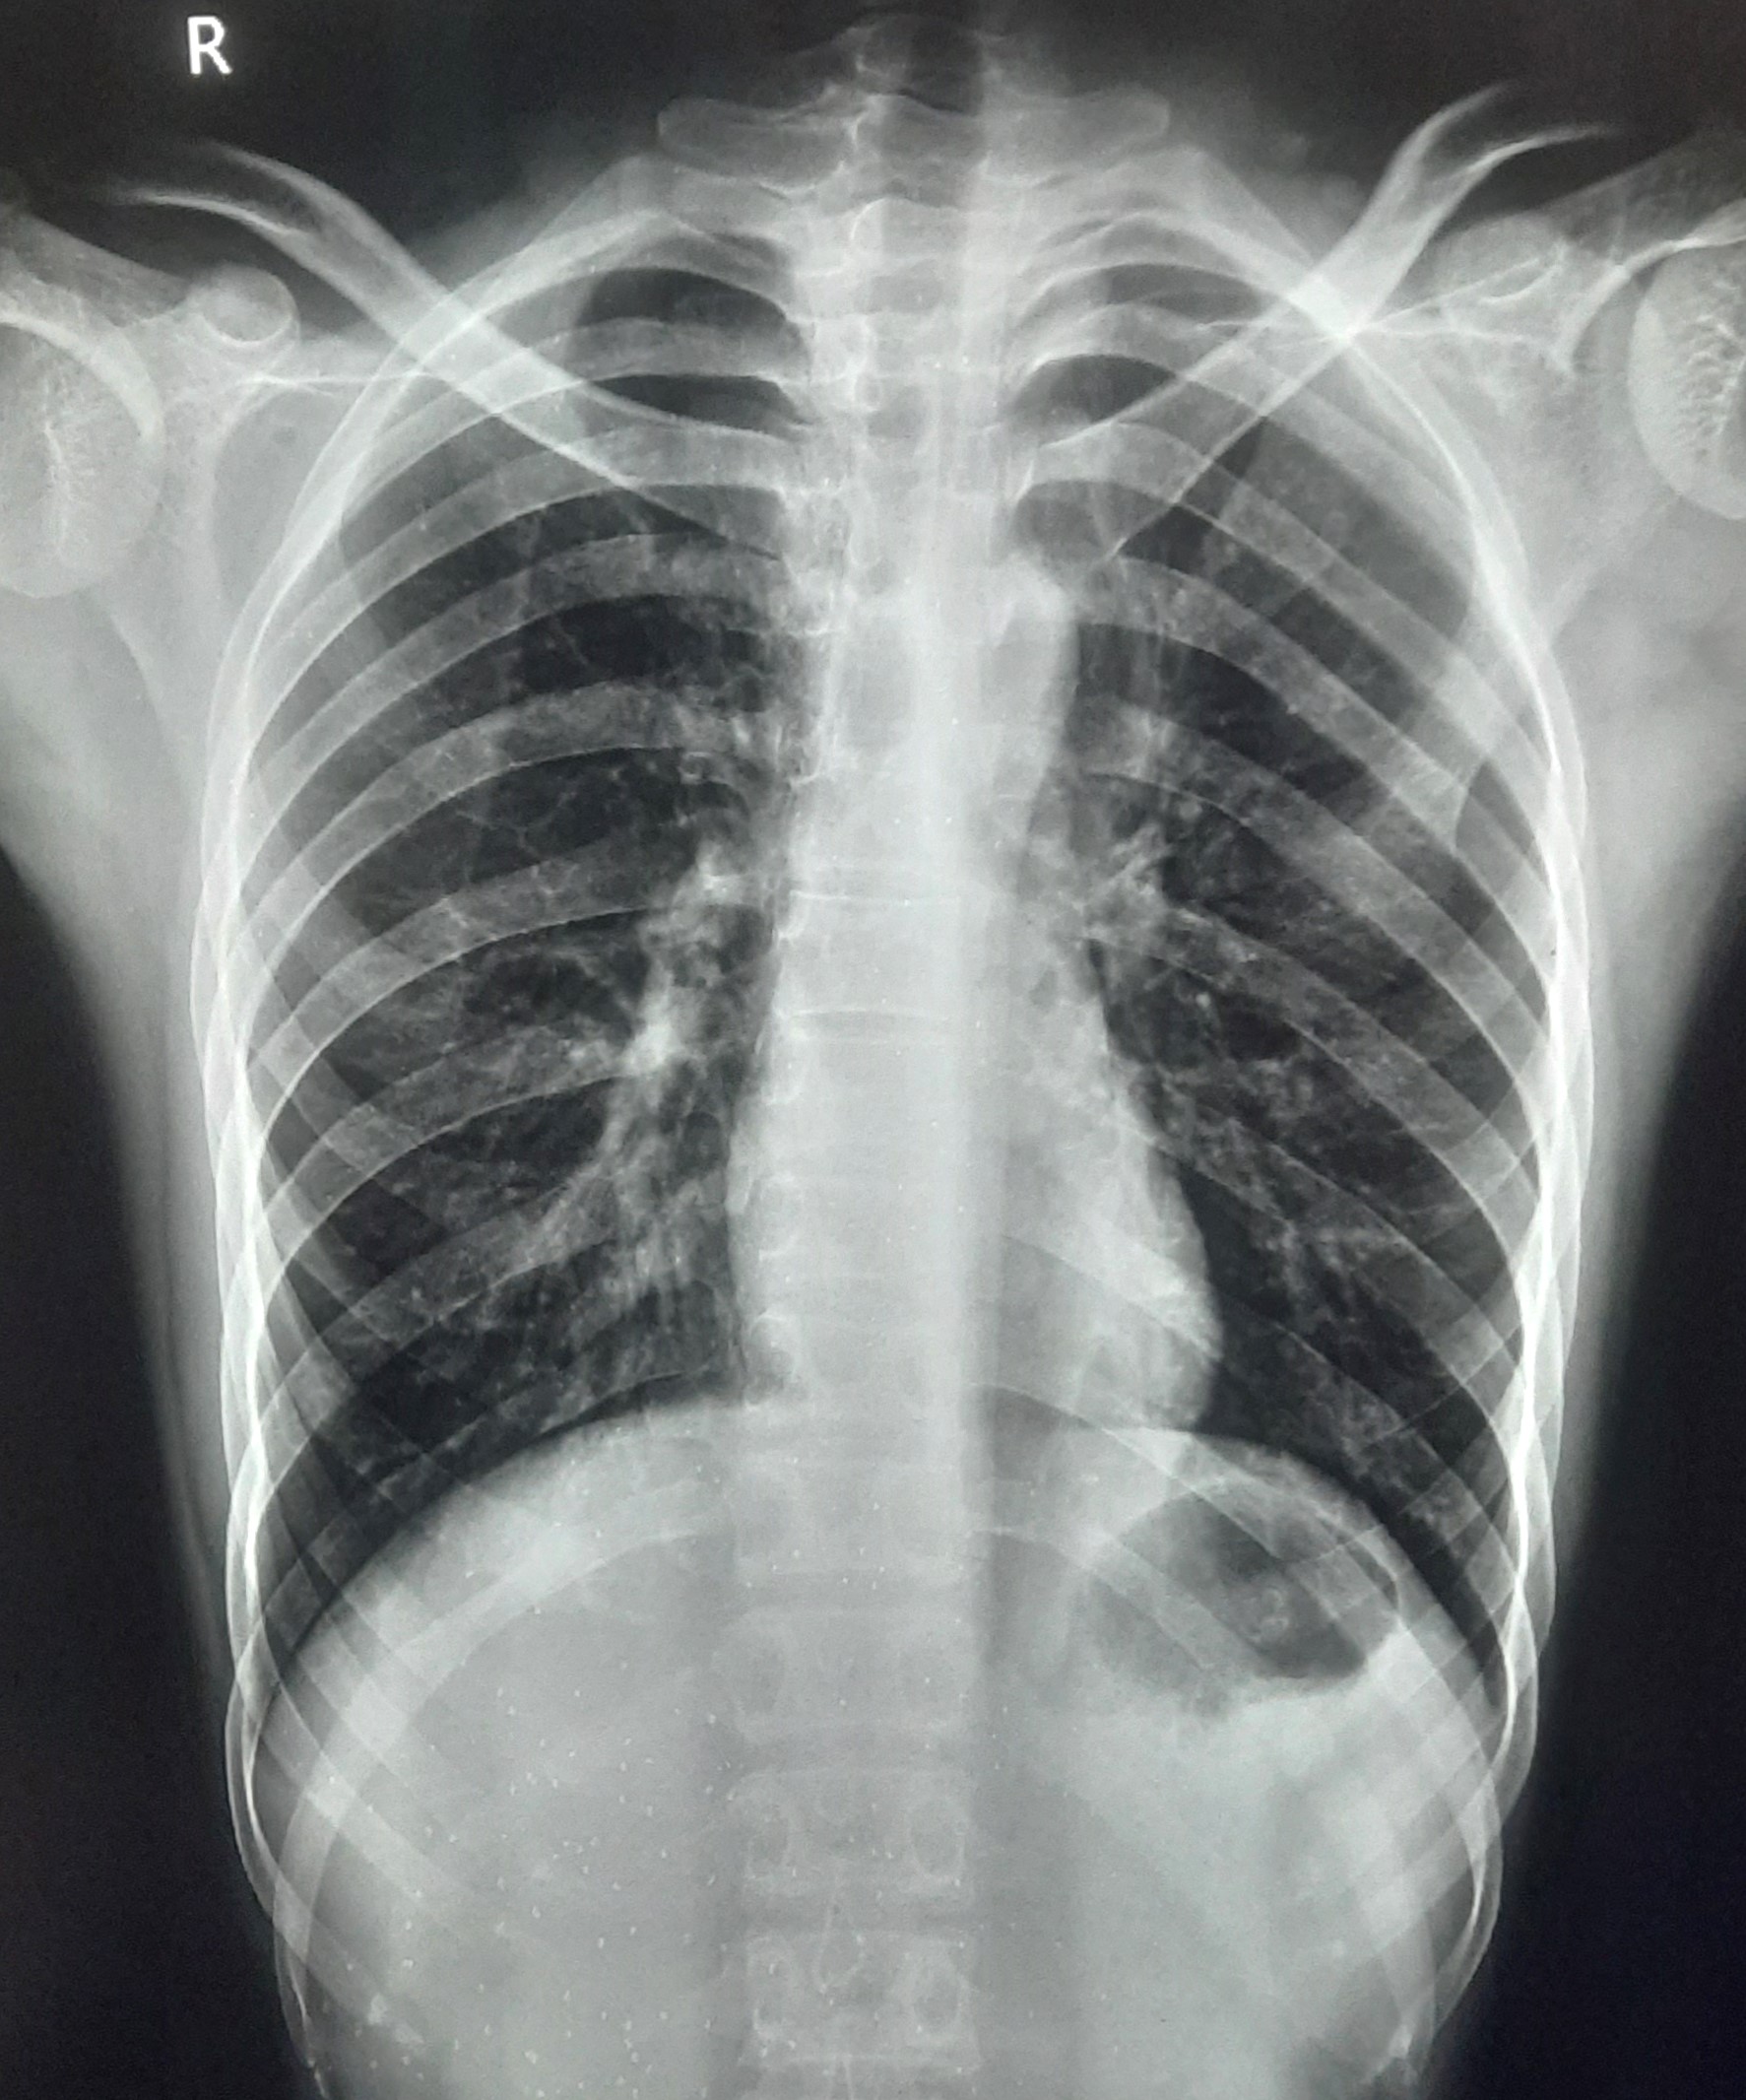

| 212 | IGGMC, Nagpur, Nagpur | P2 | 29-4260 | MALTI REVATKAR | Consent taken on Paper | 32 Yrs. |

Provisional Diag : B/L INFILTRATION ? PTB

Final Diag : Microbiologically Confirmed Pulmonary Tuberculosis |

TB Case (Confirmed) | B/L INFILTRATION | Abnormality visible on x-ray |

View |